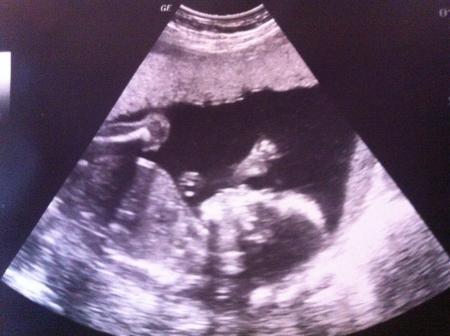

Mein FA ist auch sehr zufrieden. Diesmal gabs auch keine Mecker wegen der Gewichtszunahme. Mit dem kleinen Sonnenschein ist alles prima. Er wiegt ca. 340 g und man konnte sogar schon die 4 kleinen Finger und den Daumen sehen! Ein Oberschenkel wurde mit 3,2 cm vermessen und die ganzen anderen Zahlen hab ich vor Faszination vergessen. Das Baby liegt bei mir quer einmal über dem Bauchnabel. Der Arzt meinte, er (also das Baby ;)) müsste jederzeit entweder mit Kopf oder Po rumrutschen, ansonsten müsse man das beobachten. Hat 1.QL in den MuPa geschrieben. Mein Würmchen scheint gerade sehr aktiv zu sein, weil ich die Bewegungen gestern deutlich tiefer gespürt (und gesehen!!! ) habe.

Ich hab gerade nochmal ein bisschen gelesen. Kein Grund zur Sorge: Babys drehen sich noch ganz viel hin und her und selbst Tage vor ET kann sich die Lage noch ändern. Also alles gut. :) Ich hatte von dem einem zum anderen FA-Termin innerhalb von 2 Wo = 3 kg zugenommen. Wiege aber auch nichtmal 60 kg. War ihm wohl proportional gesehen, etwas viel. Jetzt hat sich das aber wieder normalisiert. Hab auch nicht vor, jetzt in der leckeren Weihnachtszeit auf irgendwas zu verzichten. Anbei ein Foto von meinem Boxer-Baby

oh ja die böse querlage :-D naja mach dich nicht verrückt. machst du offensichtlich auch nicht ;-) schön das sonst alles prima ist! super Bild